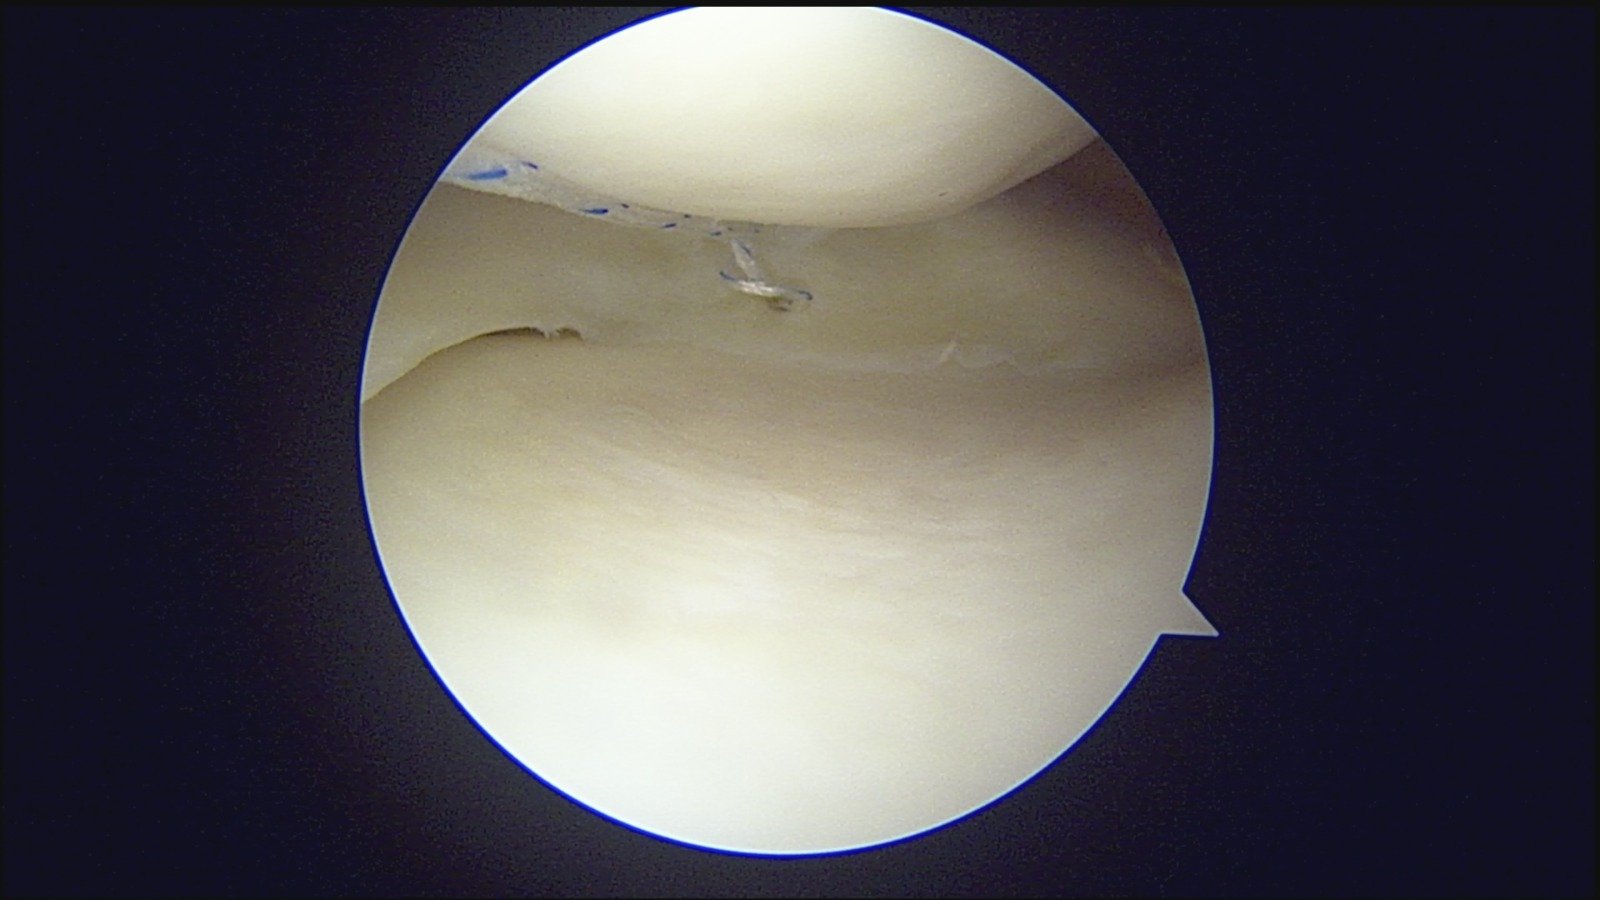

GalleryShoulder rotator cuff repair Meniscus root repair Meniscus repair Bankart repair for recurrent shoulder dislocation ACL reconstruction Machines Instruments